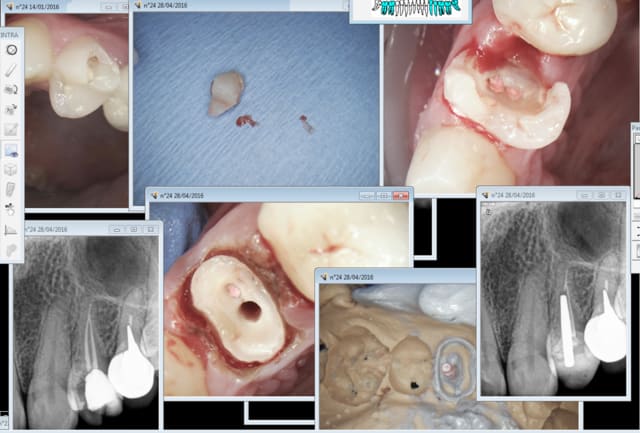

Ce que tu fais ? endo empreinte ic coiffe dans la séance.

1H 30 : pose ic coiffe 11 13 14 ( manque la 12 fait chier) endo taille empreinte 15 24 25.

Propre net sans bavures. -)

patiente CMU, tarif CMU rien à secouer. La rapidité te sauve.